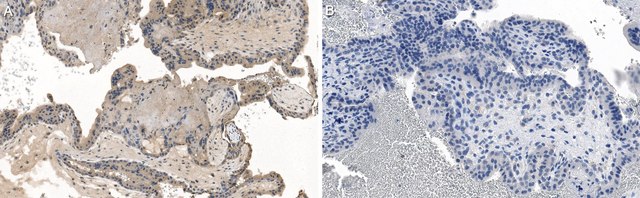

Immunohistochemistry (Paraffin) Analysis: A 1:50 dilution from a representative lot detected PDGF-BB in human placenta tissue sections.